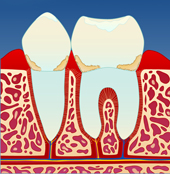

Utviklingen av periodontitt Mangelfullt renhold kan gi en overfladisk betennelse i tannkjøttet ( gingivitt ). Tannkjøttet blir da hovent og får en mørkere rødfarge. Det vil også blø ved berøring og føles ømt. Dette skyldes bakterier og mykt belegg som blir liggende langs tannkronen (I).

| |  | |  | |  |

| figur I | | figur II | | figur III | | figur IV |

Dersom belegget ikke fjernes, vil det over tid forkalkes og bli hardt. Det er dette vi kaller tannstein. Tannstein forsterker betennelsen som fører til at benet rundt tennene brytes ned (II). På denne måten vil tannstein og bakteriebelegg kunne strekke seg stadig lenger ned langs rotoverflaten (III). Bentapet kan over tid bli så omfattende at tenner løsner og eventuelt må fjernes (IV).